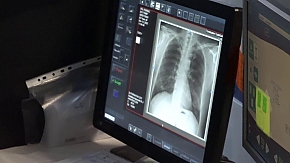

A felvételeket menet közben töltötték fel az on-line rendszerbe, ahol a leleteket folyamatosan értékelik a tüdőgyógyintézet munkatársai. Az eredményeket a felvétel után 3-4 héttel ismerhetik meg a résztvevők. Nem kell megijedni, ha valakit kiegészítő vagy kontrollvizsgálatra hívnak vissza, mivel a legtöbb esetben csak arról van szó, hogy valamiért nem sikerült jól a felvétel.